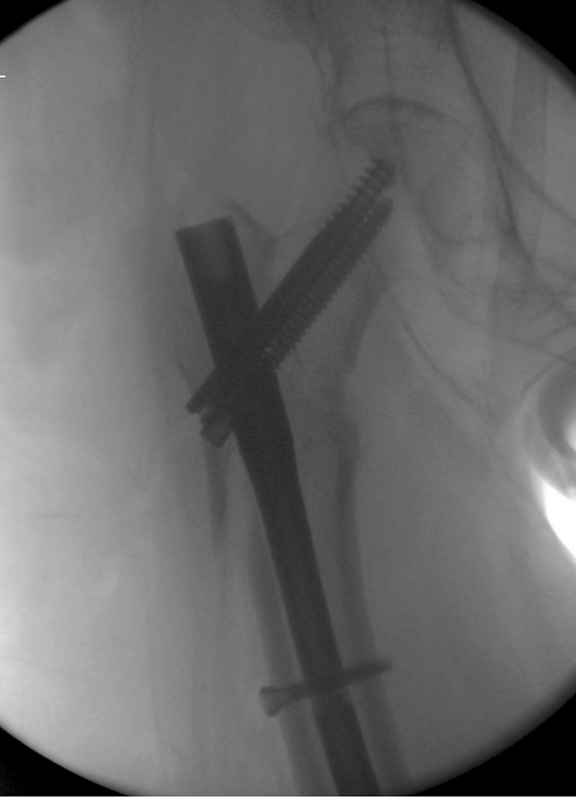

Здесь пара случаев фиксации похожих переломов:

первый высокоэнергетическая травма 36 лет